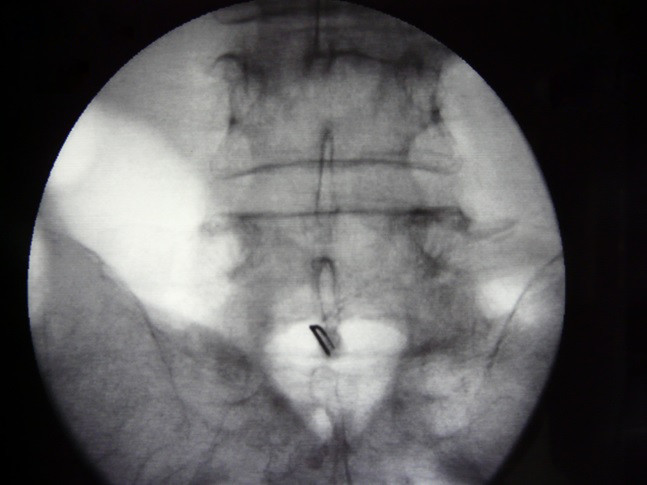

Fig.5. La posición correcta de la punta de la aguja de Chiba se corrobora mediante la administración de 3 ml de medio de contraste, y se realiza bloqueo con 5 ml de bupivacaina al 0.5%, previo a la administración del agente neurolitico 8 ml de fenol al 10%.

6/6